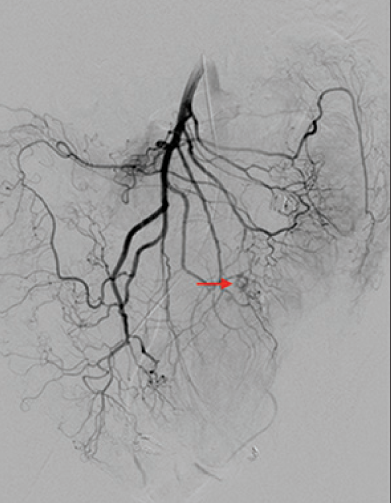

抗凝剂:肝素 溶栓药物:尿激酶、阿替普酶 ![]() 7 名患者 在动脉内内给予托拉唑啉、肝素、尿激酶进行血管造影操作 2 名患者出现出血性诱因情况 外科治疗 ![]() 回顾性分析(2002 年至 2008 年) 34 名患者(年龄 7 至 92 岁),36 例刺激性肠造影检查 全身性使用肝素 动脉内给药的血管扩张剂 11 名患者(占 31%)出现出血情况的检测结果。 10 栓塞治疗 病例1 消化道大出血 血压 70/40mmGg

病例三 77岁女性复发性胃肠道出血,需要多次输血并入住ICU。(d)栓塞后无外渗。箭头指向栓塞部位。

激发试验药物剂量和结果![]() 、、 ![]() 本文是一篇发表在《Journal of Gastrointestinal Surgery》上的研究通讯文章,题目为“Provocative Mesenteric Angiography: Outcomes and Standardized Protocol for Management of Recurrent Lower Gastrointestinal Hemorrhage”。该研究旨在评估激发肠系膜血管造影(PMA)在复发性下消化道出血中的有效性和并发症,并探讨是否可以在多学科环境中建立一种技术操作规程。 研究方法研究团队回顾了其机构在过去12年(2008年至2020年)期间进行的下消化道出血肠系膜血管造影的数据,基于CPT代码75726筛选出符合条件的病例。进一步分析了其中的PMA病例,排除了医源性、手术性或创伤性原因引起的下消化道出血。挑衅性造影的诱导方案包括使用硝酸甘油扩张血管、肝素抗凝以及组织纤溶酶原激活剂(tPA)溶解血栓。 研究结果在12年的研究期间,共进行了36例PMA。其中16例(44%)为阳性结果,20例(56%)为阴性结果。阳性组和阴性组之间在患者人口统计学特征、既往下消化道出血史、先前住院次数、Charlson合并症指数评分或术前血红蛋白水平方面没有显著差异。所有阳性病例均接受了栓塞治疗,且无出血并发症,无再出血事件,也未出现缺血性肠病后遗症。尽管有两名患者(12.5%)在30天内因复发性出血再次入院,但这一比例显著低于在阴性研究中再出血的60%。 结论本研究是迄今为止最大的文献,表明PMA在适当选择的患者中能够成功诱发和治疗下消化道出血。此外,该程序是安全的,即使使用较高剂量的tPA,也没有发生出血或缺血性肠病并发症。研究机构采用了一种修改后的现有社会指南协议,将PMA纳入下消化道出血的管理流程。 其他信息文章还提到了一些相关的参考文献和被引用的文章,涉及早期与标准结肠镜检查、急性下消化道出血的门静脉造影预测因素和结果、隐匿性胃肠出血的挑衅性肠系膜血管造影更新等内容。这些文献提供了更多的背景信息和相关研究支持。 激发血管造影并发症 与“激发”试验直接相关的并发症